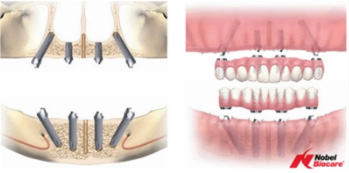

オールオン4とは、インプラント治療の一種で、総入れ歯の方や多くの歯を失った方が対象の治療です。4本のインプラントを顎の上下に埋入することで全ての歯を取り戻すことができます。特に当院が提供しているオールオン4の場合、骨の移植の必要がなく、抜歯からインプラントの埋め込み、仮歯の装着までがその日のうちに完了します。それまで使用していた歯や入れ歯がたった1日で、新しく埋め込んだインプラントに支えられている仮歯に代わり、しっかりと噛んで食事をとることができるようになるという、最新の治療となっています。

- 片顎につき4本のインプラントを埋入して10〜12本の歯を支える

骨の状態により場合によっては6本のインプラントを埋入する場合がある(オールオン6)

オールオン4

オールオン6